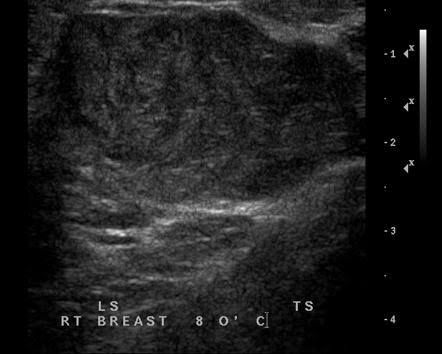

Experts don't know what causes phyllodes tumors. Women who have a rare genetic disease called Li-Fraumeni syndrome are more likely to have them. They rarely affect men. Women of any age can get phyllodes tumors, but they're most common in your 40s.